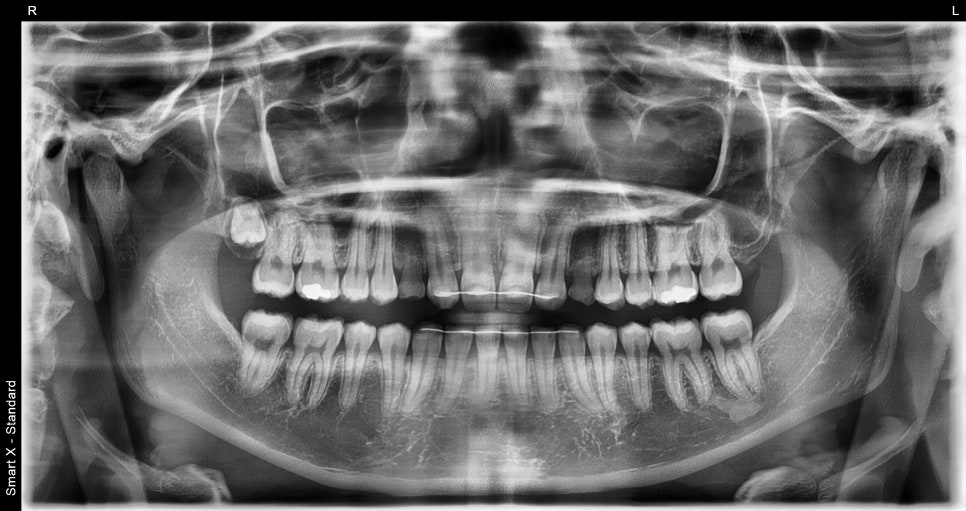

A patient in their 20s with concerns about their teeth

This patient visited us because they were concerned about the shape of their teeth

and their overall appearance.

Checking the condition of the teeth and taking photos